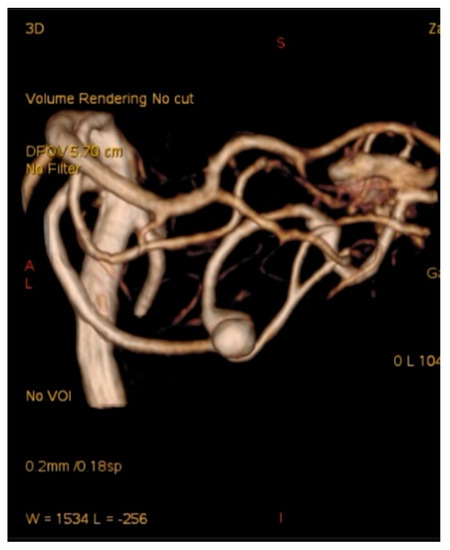

2.6. SCA Aneurysms and AVM

A 58-year-old woman with sudden onset of headache and vomiting was admitted to hospital. The CT scan showed subarachnoid hemorrhage (Fischer grade 3), and the CT angiogram revealed AVM with an associated aneurysm on the left superior cerebellar artery (Figure 9). Endovascular treatment was indicated, and successful Onyx embolization of AVM and coil embolization of the aneurysm was performed (Figure 10). The postoperative course was also without complication, and the patient is followed up.

Figure 9. Computer tomography angiography with aneurysm of the left SCA associated with cerebellar AVM.